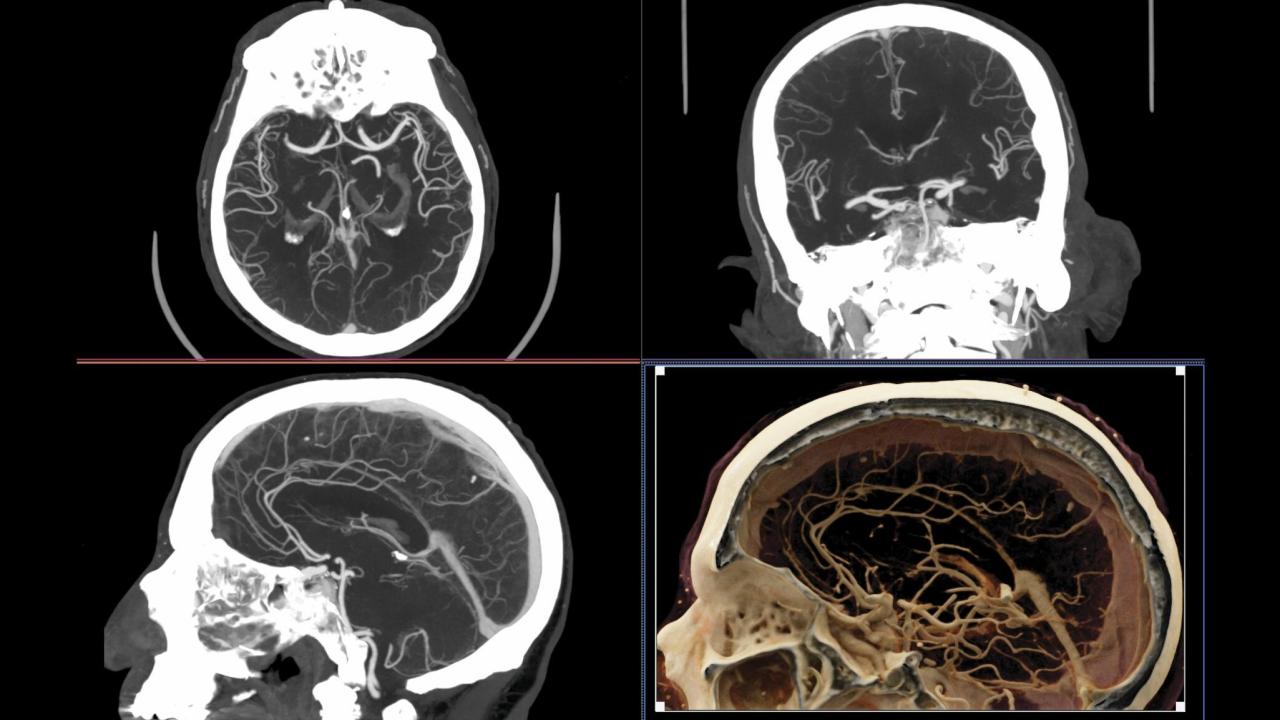

Four images of a human head made by CT imaging.

CT imaging of blood vessels in the brain. Lower right image shows a volumetric reconstruction. (Cynthia McCollough, Mayo Clinic, via Physics Today)

CT scans use thousands of X-ray images to build a three-dimensional image of the body. The technology has revolutionized medicine, allowing physicians to see inside a patient without exploratory surgery. More than 90 million medical CT scans are carried out every year in the U.S.

Boone and McCollough describe the principles behind CT scanning and the advances made in the technology in the past 50 years. At first, it was only practical to image the head, as a patient’s head could be immobilized for the several minutes needed to complete a scan. Today, advances in the arrangement of X-ray sources and detectors have made it possible to scan the entire torso from chest to pelvis in five seconds. The most advanced systems can resolve features as small as 150 microns.